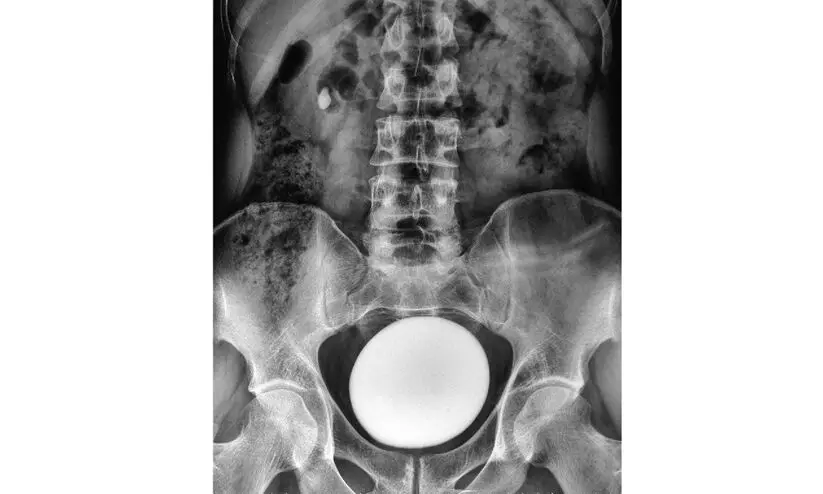

മൂത്രാശയക്കല്ല്: കാരണങ്ങളും പരിഹാരവും

● കല്ലുകളുടെ ഘടന- കാൽസ്യം ഓക്സലേറ്റ് - 70-80 %, കാൽസ്യം ഫോസ്ഫേറ്റ് - 15 %, യൂറിക് ആസിഡ് - 8 %, സിസ്റ്റിൻ - 1 മുതൽ 2 % വരെ